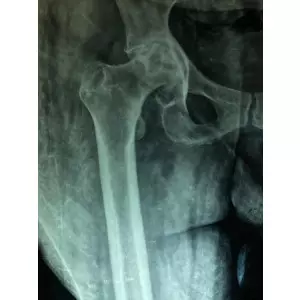

Dr Samir Nanavati